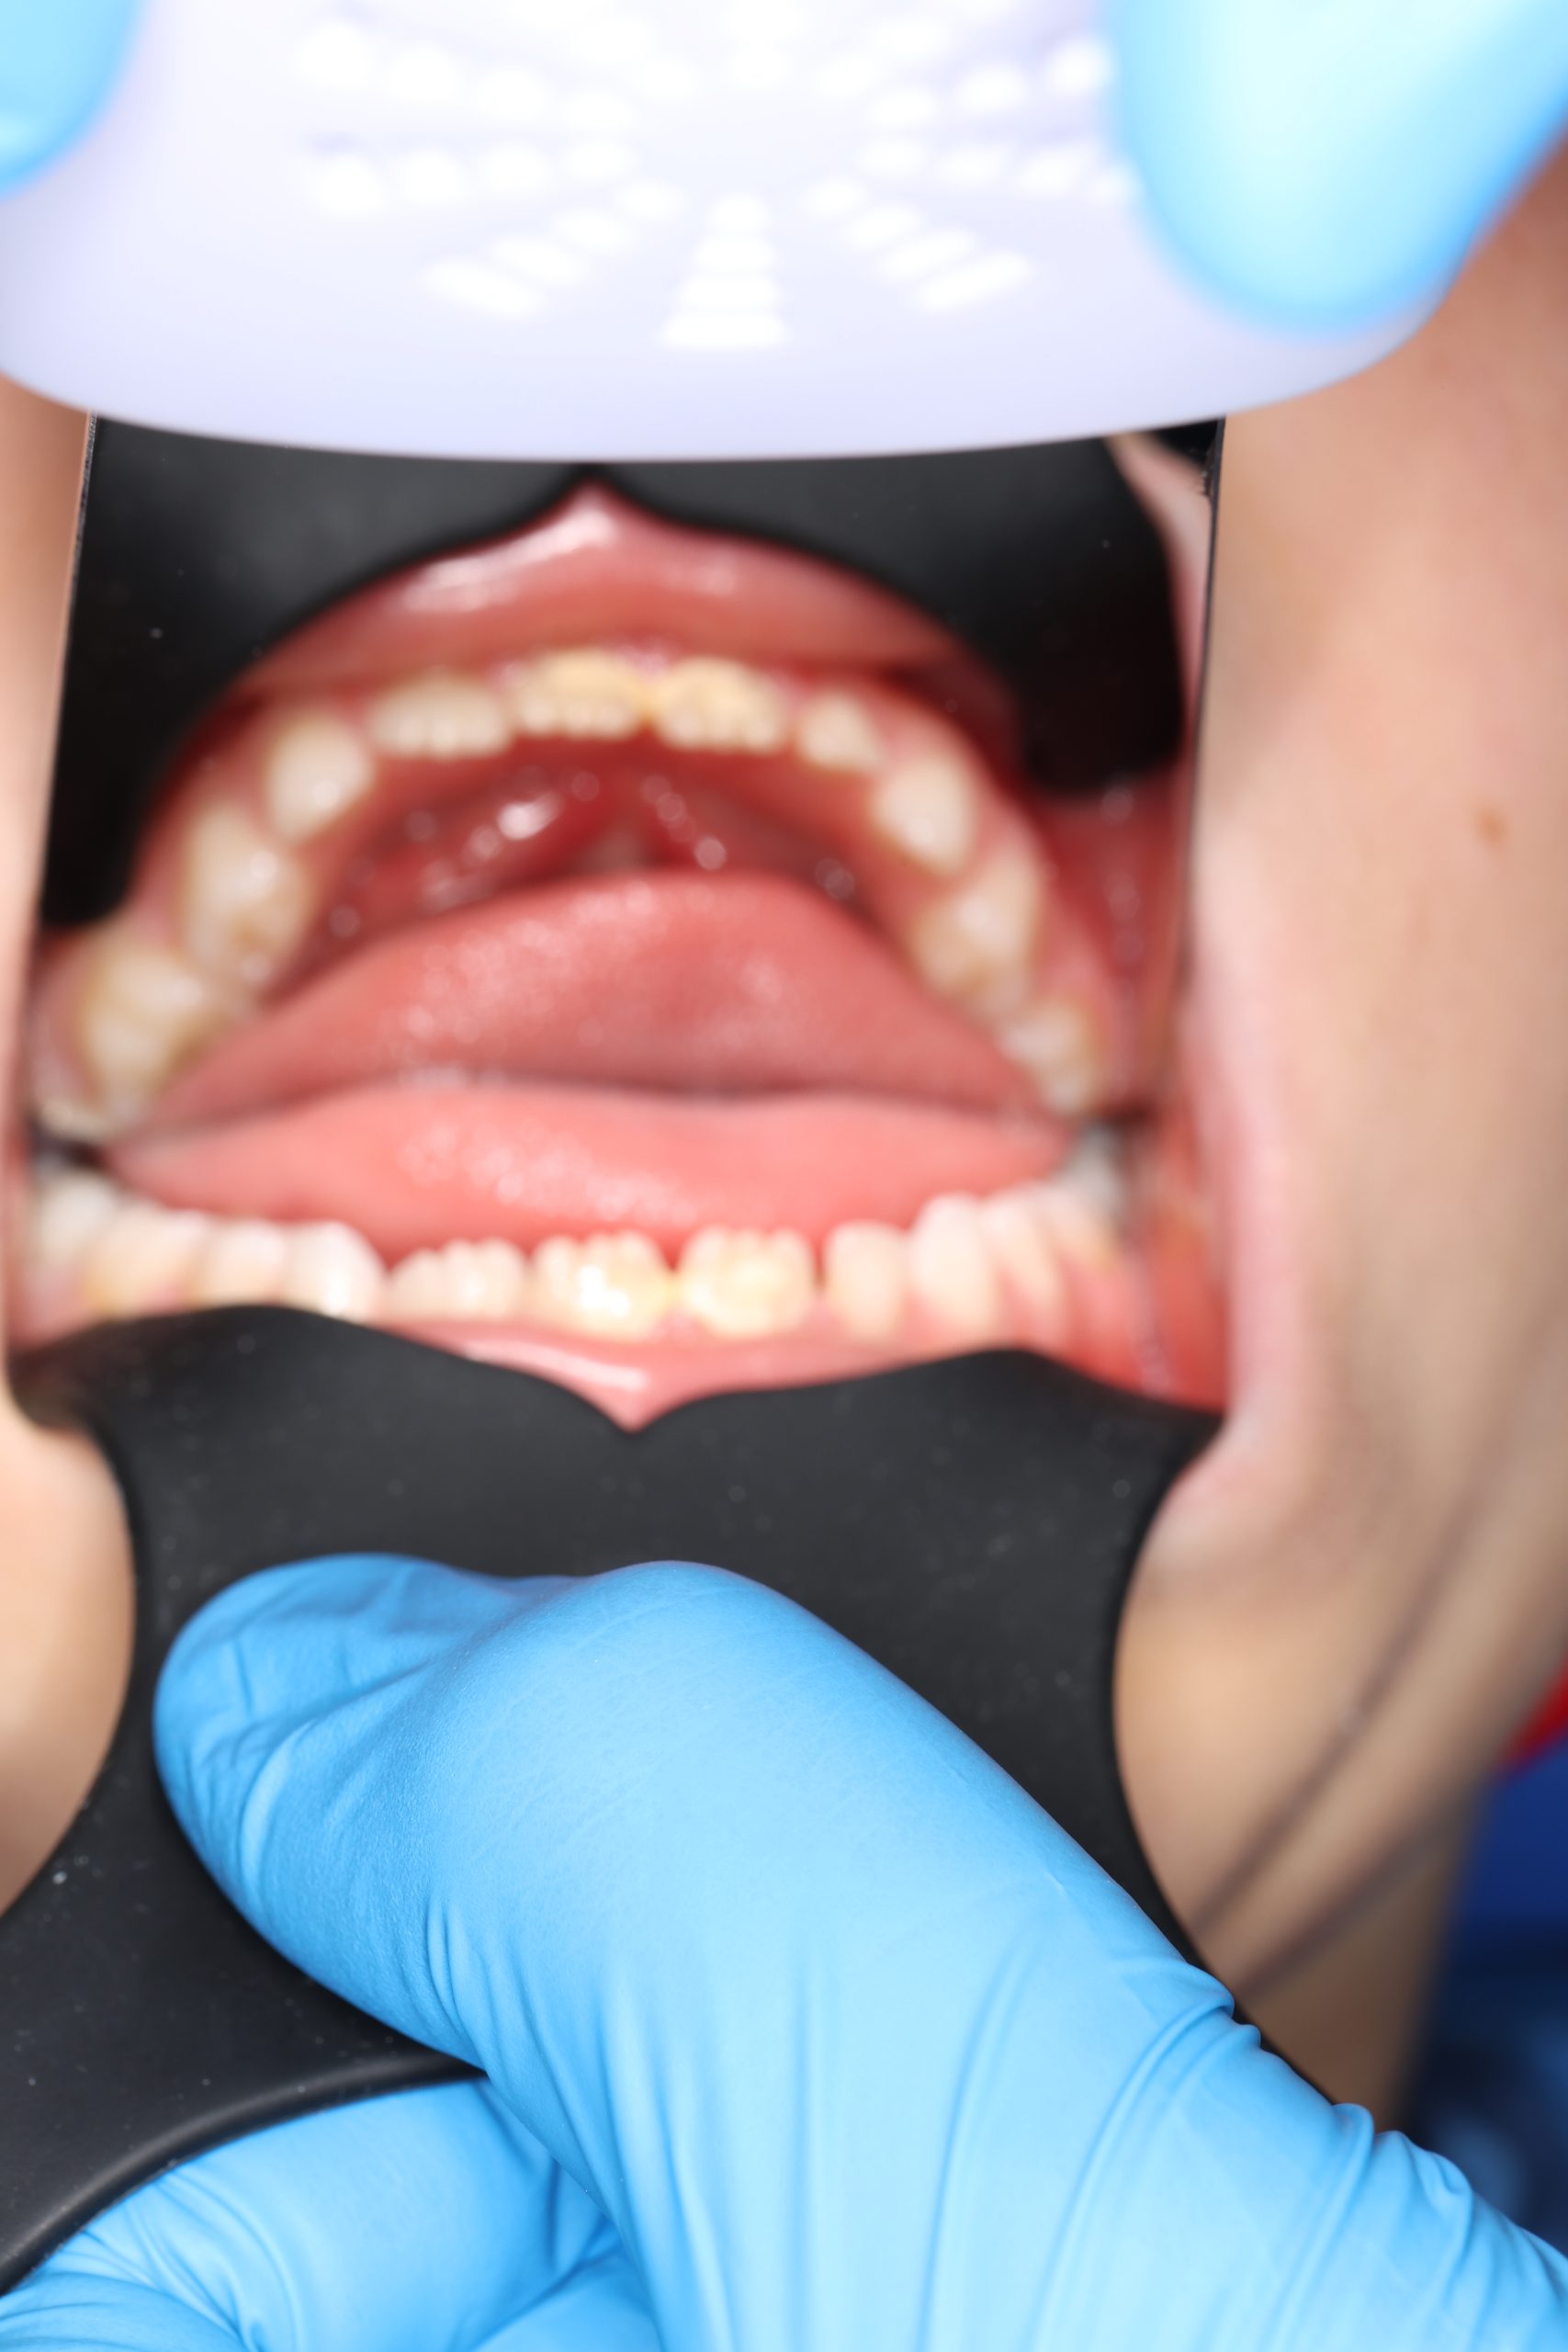

Together with your child, we practice brushing techniques, correct mistakes, and provide personalized recommendations. We advise whether to use manual or electric brushes, floss, interdental brushes, or remineralizing gels. - Plaque Removal with AIRFLOW Prophylaxis Master (EMS, Switzerland)

From age 4–5 and up, we perform full GBT cleaning using an ultra-fine erythritol powder to clean even hard-to-reach areas gently and safely. It does not damage enamel and is ideal even around braces — no need to remove brackets or wires. - Tartar Removal (If Needed)